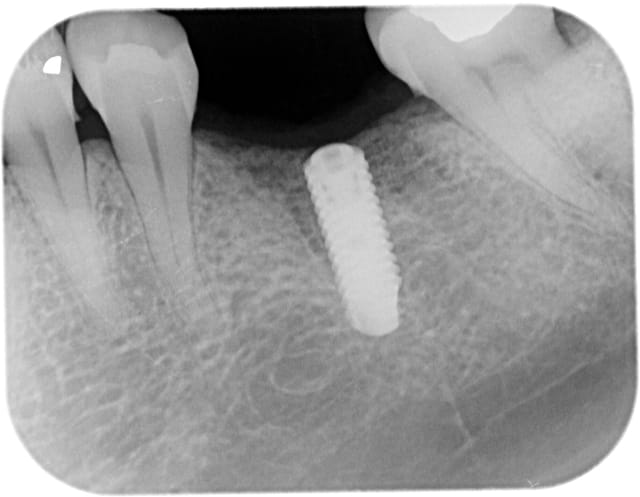

comme ce petit cas

la 2ème radio est prise 18 mois après la 1ère

PS pour Gulguch c'est bien un implant de 6 mm de diamètre en distal et pourtant pas la moindre perte osseuse...